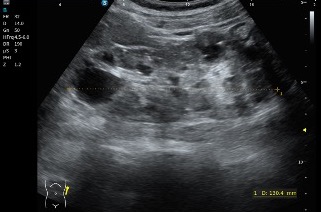

En este caso iniciamos la exploración con sonda convex, siguiendo el protocolo habitual de ecografía abdominal y, al valorar el parénquima hepático, rápidamente llama la atención un hallazgo muy característico que es el que pasamos a describir a continuación.

- Número prácticamente incontable de lesiones

- Morfología redondeada

- Contenido anecoico

- Bordes finos, lisos y bien definidos

El patrón era bastante típico y, según el criterio del radiólogo, correspondía a múltiples quistes hepáticos, como queda reflejado en las imágenes ecográficas (imagen 1 e imagen 2).